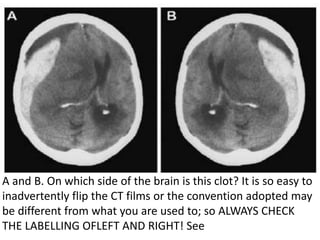

A and B. On which side of the brain is this clot? It is so easy to

inadvertently flip the CT films or the convention adopted may

be different from what you are used to; so ALWAYS CHECK

THE LABELLING OFLEFT AND RIGHT! See

Schematic illustration showingthe difference between acute epidural haematoma (A) and acute subdural haematoma (B). Can you confidently distinguish the AEDH from the ASDH?

• 106.

A and B.On which side of the brain is this clot? It is so easy to inadvertently flip the CT films or the convention adopted may be different from what you are used to; so ALWAYS CHECK THE LABELLING OFLEFT AND RIGHT! See